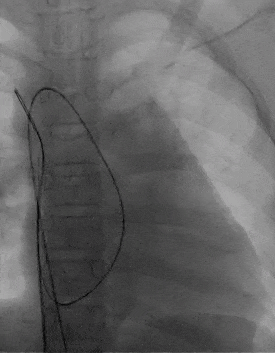

展开左右盘面

左盘展开

右盘展开并造影

基本无残余分流

释放前超声

释放前超声下封堵器型态良好,骑跨室间隔两侧